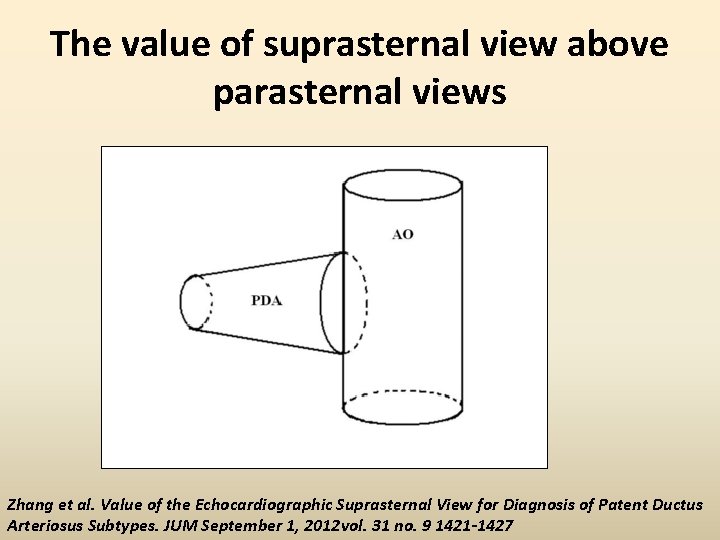

The value of suprasternal view above parasternal views Zhang et al. Value of the Echocardiographic Suprasternal View for Diagnosis of Patent Ductus Arteriosus Subtypes. JUM September 1, 2012 vol. 31 no. 9 1421 -1427

Measurements from the suprasternal view -Ampulla -Adjacent aortic diameter.